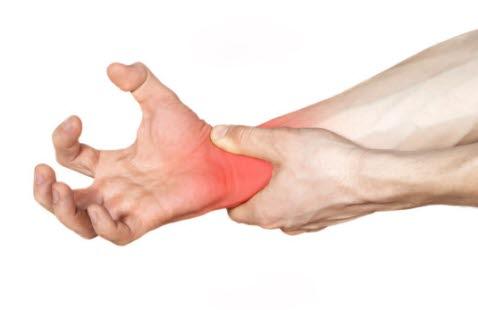

Brudd i båtbeinet, skafoidbeinetBåtbeinet, som på fagspråket kalles skafoidbeinet, er et av beina i håndroten. Ved fall på strak arm der du forsøker å ta deg for, kan det oppstå brudd i dette beinet. I nærmere 90% av tilfellene med brudd i håndroten, er det båtbeinet som ryker (se tegning). Det gir ømhet og smerter i håndroten, og du kan kjenne en dyp, vag smerte på tommelsiden av håndleddet. Smerten som ofte er mild, forverres ved å gripe eller klemme med hånden.